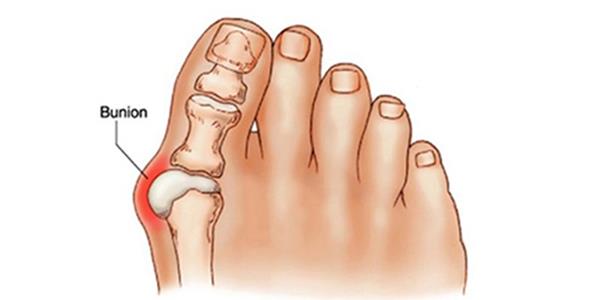

무지외반증은 말은 어렵지만 결국 뾰족한 구두를 주로 신다가 엄지발가락이 구두에 맞게 휘어져 생기는 병이다 (나의 경우에는) 물론 무지외반증은 선천적인 요인과 후천적인 요인 등의 복합적 요인으로 생길 수 있는데 선천적으로는 평발과 넓적한 발 , 과도하게 유연한 발 또는 유전적 요인으로 생길 수 있으며 후천적으로는 신발 앞이 좁은 신발을 신거나 하이힐 등의 굽이 높은 신발을 주로 착용하는 경우 생길 수 있다.

무지외반증은 엄지 발가락이 검지발가락 쪽으로 휘어지면서 엄지발가락 바깥쪽 끝 부분이 과하게 튀어나오게 된다. 이 튀어 나오게 된 부분이 신발 등에 자극을 지속적으로 받으면서 통증이 생기고 염증이 일어나게 되는데 심하면 엄지발이 휘어지면서 검지발가락과 다른 발가락에도 변형을 주거나 압박을 주어 피부 궤양이 발생하거나 탈구, 변형 등이 생기기도 한다.